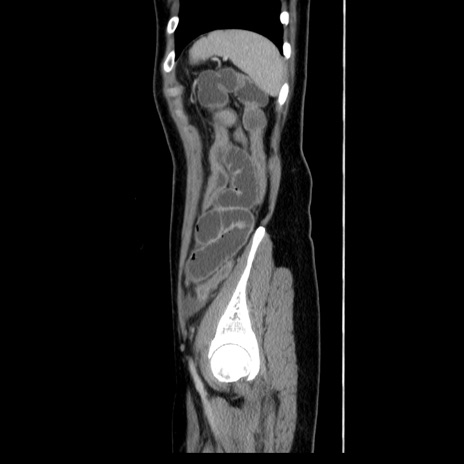

症例39(矢状断像)

【症例】40歳代女性

【主訴】上下腹部痛

【現病歴】2日目から下腹部痛あり。夜間は痛みで眠れなかった。昨日より上腹部痛と下痢が出現。臥位で痛みは軽快したため、休んでいた。本日になって臥位でも立位でも痛みが強くなってきたため救急要請。

【既往歴】子宮内膜症

【身体所見】部:平坦・軟、左上下腹部に圧痛あり、反跳痛あり。

【データ】WBC 21800、CRP 26.78

CT